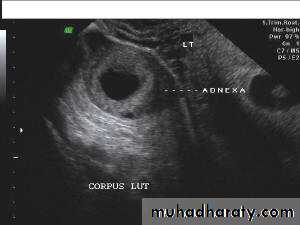

• Functional cysts of the ovary – Corpus Luteum cysts

Lt. adnexal cystic mass- Luteal cyst(Lt. ovary):• Functional cysts of the ovary – Corpus Luteum cysts